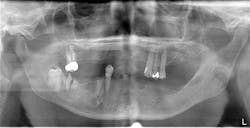

After the fabrication of full upper and lower immediate dentures, the patient underwent extraction of the remaining teeth and the placement of eight immediate dental implants (Hahn Tapered Implants, Glidewell; figure 8).

At the time of placement, ISQ readings were taken. Though the primary stability was high in these implants, the decision to allow them to integrate prior to loading was made, as each individual implant would be subjected to forces and they were not splinted. After insertion, 3-mm healing abutments were placed on all the implants except tooth No. 3, as that implant had a much lower initial stability reading. On the lower arch, 3 mm healing abutments were placed on all implants except for No. 22 due to stability. The dentures were relieved and delivered to the patient.

At one month, ISQ readings were taken of all the implants except No. 3. The lower arch showed the soft tissue healing at that time (figure 9). At 2.5 months, readings were taken again, and it was indicated that the mandibular arch had integrated and was ready for final attachment via locator attachments (Zest; figures 10 and 11). The maxillary implants were continuing to show progress, but not to the point where predictable loading was possible. Because the maxillary denture was stable (as most are), this was not an issue. The patient greatly appreciated the completion of the mandibular overdenture, which was very mobile and bothersome.

Figure 8: Post-op panorex